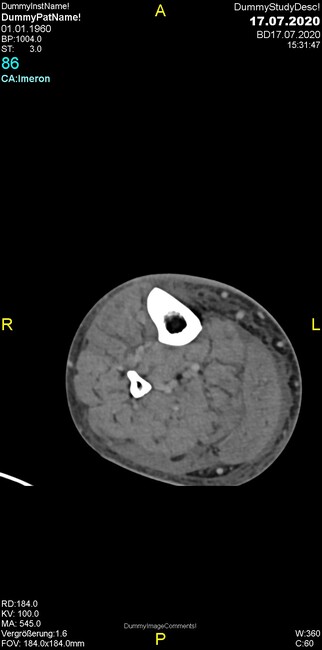

Um welche Modalitäten handelt es sich?

- Röntgen p.a. und lateral, CT coronar Knochenfenster, CT axial Weichgewebsfenster

Was fällt in der Projektionsradiographie auf?

- Aufhellungslinie in Projektion auf die Femurkondylen

Was fällt in der CT im Knochenfenster auf?

- Osteolyse der Tibiametaphyse unter Beteiligung der Kortikalis